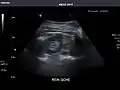

Kidneys: Right and left kidneys measure 11.5 cm and 12 cm in length respectively. No hydronephrosis. Small left lower pole kidney cyst.

Left kidney